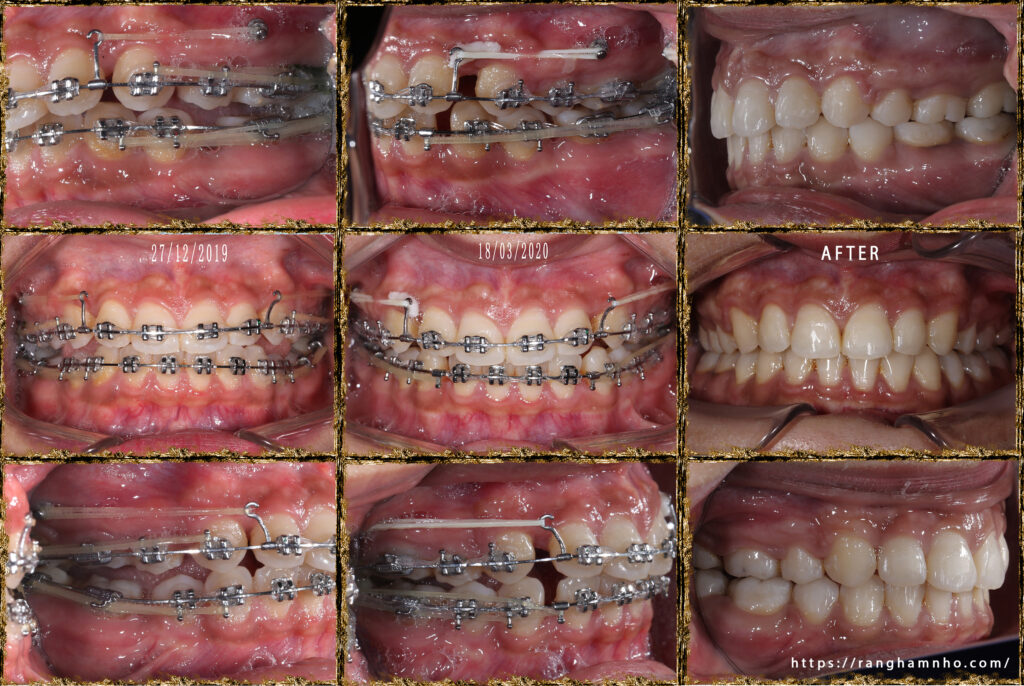

Chẩn đoán trước điều trị: sai khớp cắn hạng II, mặt hô, khớp cắn sâu. Chỉ định niềng răng nhổ 4 răng số 4 để kéo lùi nhóm răng cửa giảm hô tối đa. Có sử dụng neo chặn tuyệt đối bằng minivis chỉnh nha.

Tổng thời gian điều trị: 2 năm